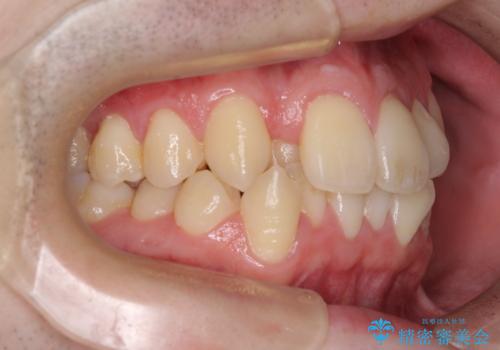

前歯のクロスバイトや八重歯の他に、左右最後臼歯のシザーズバイト(鋏状咬合)が認められました。

シザーズバイトは強く咬合する奥歯を移動させるため、多くの場合においてワイヤー矯正の装置のみでは改善が困難となります。

奥歯の咬み合わせ改善は治療初期からしっかりとアプローチする必要があるため、補助装置を積極的に利用します。